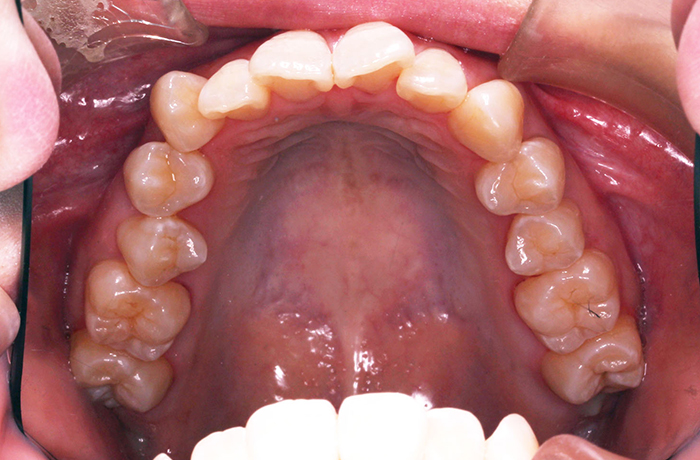

I様

治療前

before

年齢 34歳

性別 男性

治療名称 マウスピース型カスタムメイド矯正歯科装置(インビザライン)・コンプリヘンシブパッケージ(フルパッケージ)

総額治療費用 770,000円(税込) 金額備考 検査・診断料33,000円含む

治療期間 8か月 通院頻度など 40日ごと

その他治療に関する情報 1枚につき10日装着を指示しました。

患者の症状 上顎前歯の凸凹

治療方法 非抜歯で、マウスピース型カスタムメイド矯正歯科装置による矯正

治療結果 歯並び、咬み合わせが良くなりました。

その他治療に関する情報 歯並びをより良くするために追加でアライナーを発注しました。

リスク/副作用 スペース不足を解消するために歯と歯の間をわずかに削合しました。